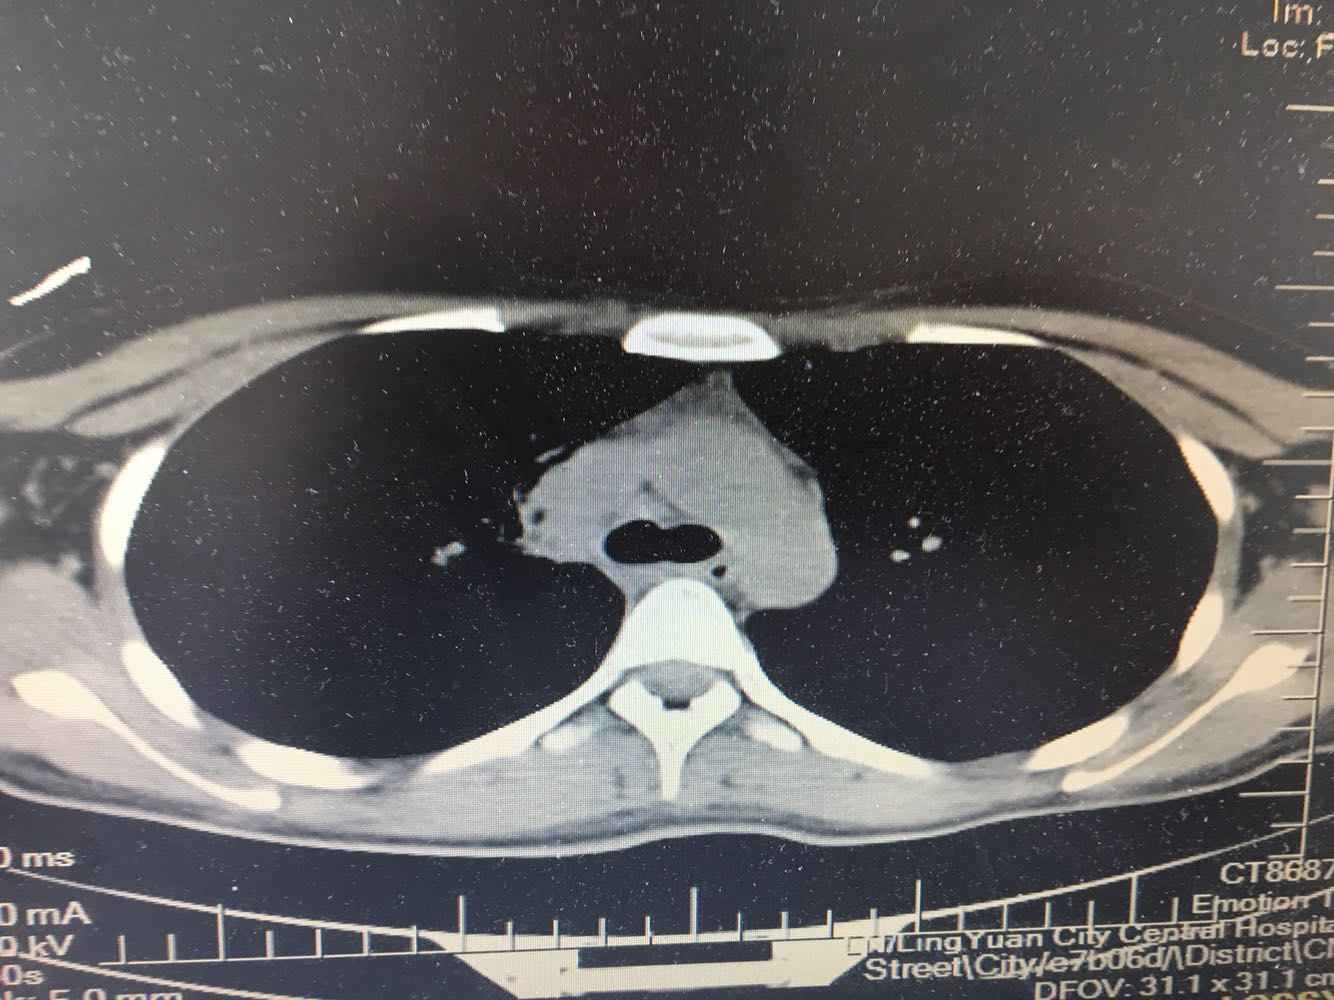

女,26岁,咳嗽1周,咳痰不畅,咽喉痒,口服阿莫西林无好转,昨日发热,体温38.5摄氏度,于门诊查肺CT后以肺炎收入院,病来无盗汗,无咳血,无消瘦及乏力,无头痛,无肢体酸痛,饮食睡眠可,二便正常

神清言明,咽部无充血,扁桃体不大,双肺呼吸音清,无罗音,服软无压痛。

支原体抗体1:160,结核抗体弱阳性。支原体肺炎个别可见上叶病变,该患无结核中毒症状,考虑支原体肺炎可能性大,但肺尖为结核好发部位,需要抗炎治疗后复查观察疗效。